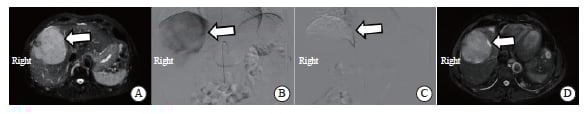

图4 TACE治疗前后疗效对比